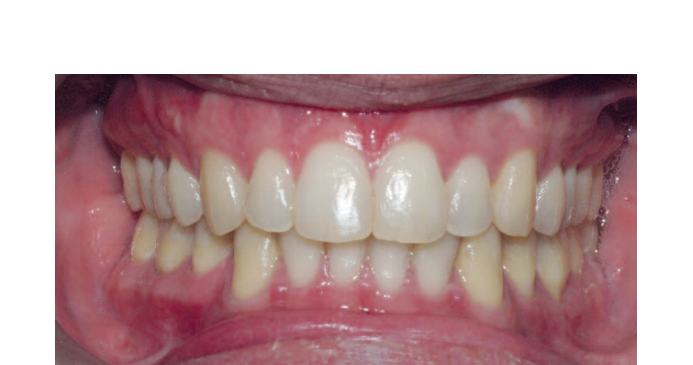

Пациент развивается удовлетворительно, и полученная окклюзия стабильна. Лицевые результаты демонстрируют явное эстетическое улучшение.

Скелетная экспансия, вызванная продвижением челюстей с противочасовой ротацией и ментопластикой, обеспечивает эстетическое улучшение, не имеющее аналогов среди других типов лицевой хирургии. Долгосрочные изменения стабильны и долговечны.